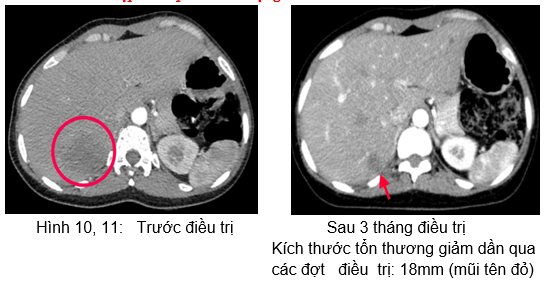

Hình 5: Tổn thương gan trước điều trị: khối giảm tỷ trọng ở hạ phân thùy S7, kích thước 37x45mm, ngấm thuốc kém sau tiêm.

- Chụp cắt lớp vi tính ổ bụng:

Hình 12: Hình ảnh CT ổ bụng sau 6 tháng điều trị: Khối nhu mô gan hạ phân thùy S7 giảm tỷ trọng, ngấm thuốc kém sau tiêm, Kích thước tổn thương giảm dần qua các đợt điều trị: và 15mm (mũi tên xanh)

Như vậy, bệnh nhân đáp ứng khá tốt với Erlotinib: chất chỉ điểm khối u, kích thước tổn thương phổi, tổn thương gan có xu hướng giảm dần.